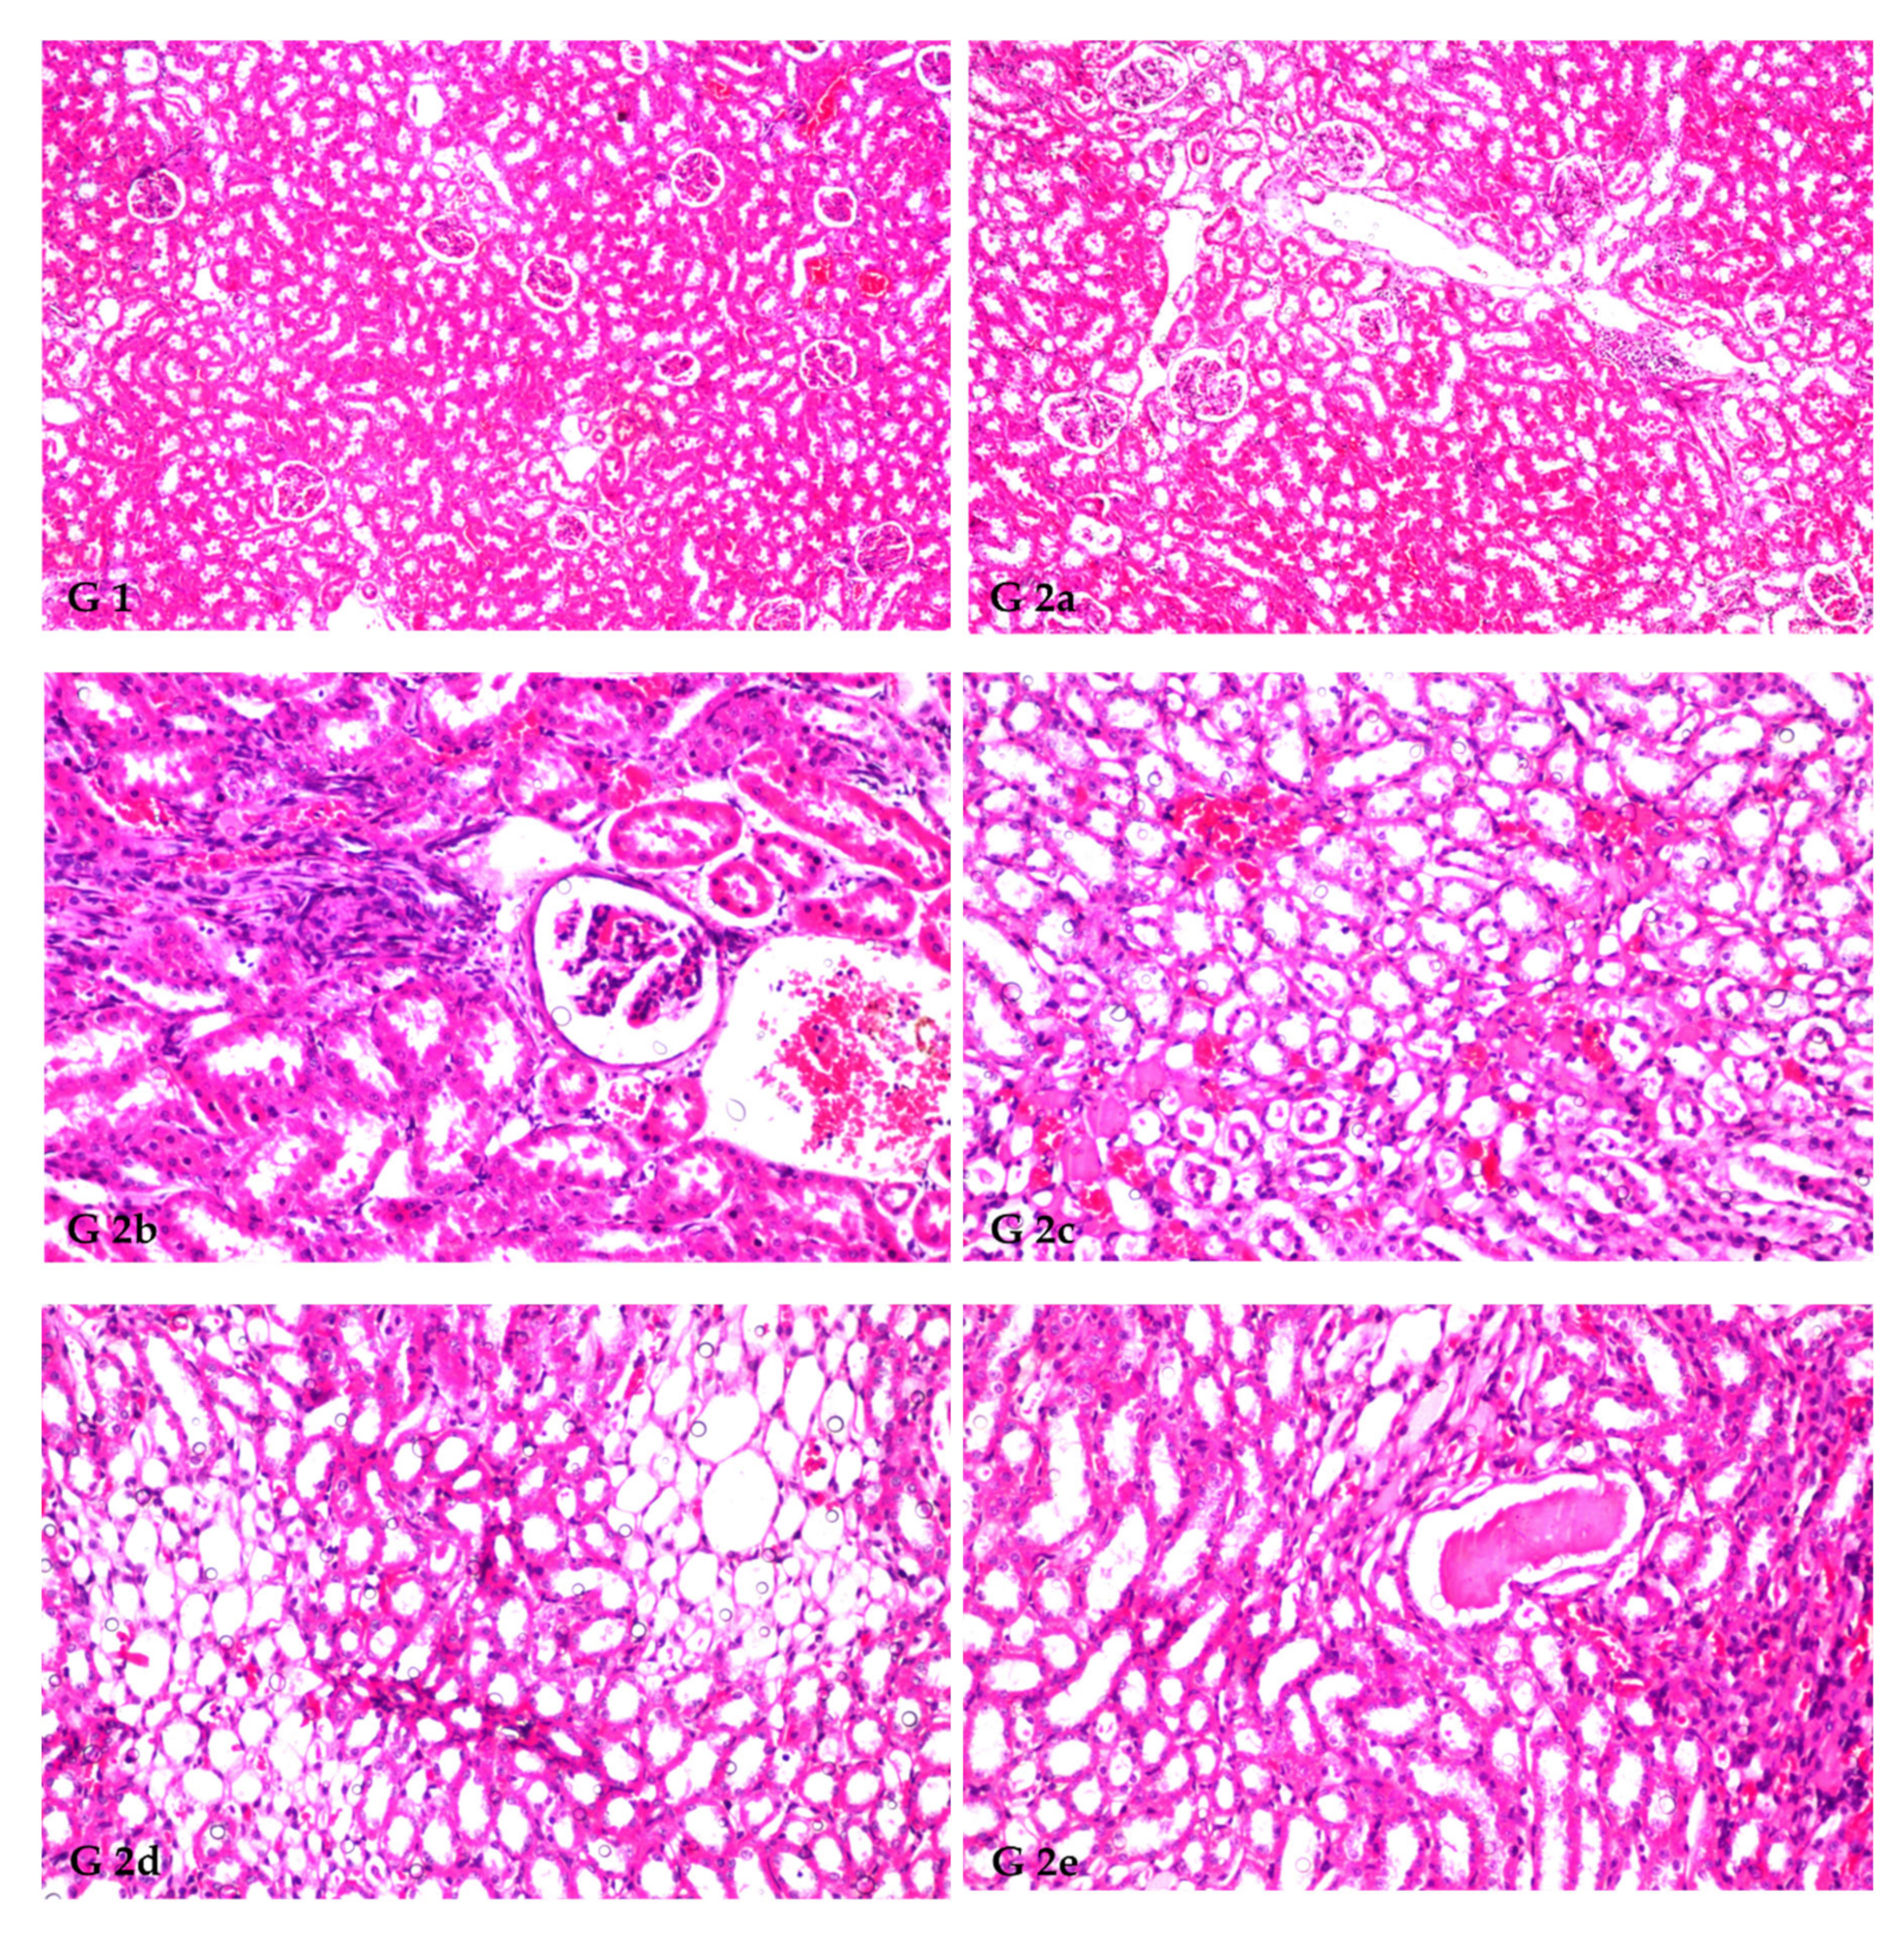

3.8. Renal Histoarchitecture